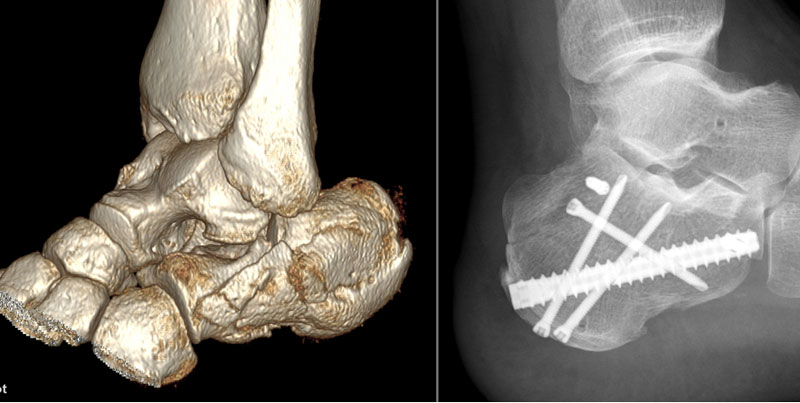

【技術(shù)突破】菏醫(yī)附院骨科創(chuàng)傷中心成功開展微創(chuàng)新技術(shù)——閉合復(fù)位“釘中釘”內(nèi)固定術(shù)治療跟骨粉碎性骨折

近日,菏澤醫(yī)專附屬醫(yī)院骨外科(創(chuàng)傷中心)成功為一名左跟骨粉碎性骨折患者實(shí)施“閉合復(fù)位釘中釘內(nèi)固定術(shù)”。該手術(shù)以微...